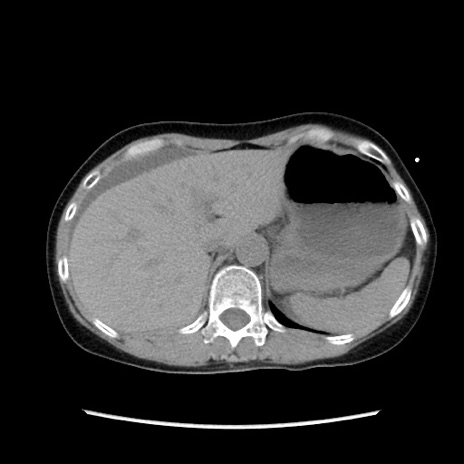

症例32(横断像)

【症例】40歳代 女性

【主訴】上腹部痛、嘔気・嘔吐

【現病歴】約9時間前頃から急に上腹部痛、嘔気、嘔吐が出現。改善しないため救急要請。

【既往歴】子宮頚癌(広汎子宮全摘術、放射線療法)、腸閉塞

【身体所見】腹部:平坦、軟、腸雑音亢進、上腹部を中心に腹部全体に圧痛あり。

【データ】WBC 8400、CRP 0.03